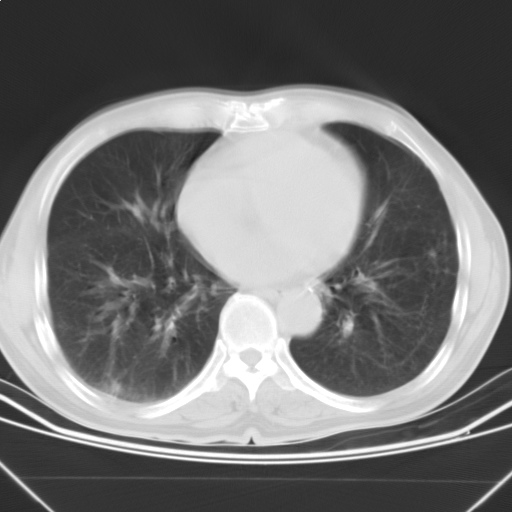

以下是引用随光逐影在2009-5-1 13:53:00的发言:[br]考虑为:1)两肺血行播散型肺结核;2)右肺下叶炎症感染。3)右侧胸膜增厚。